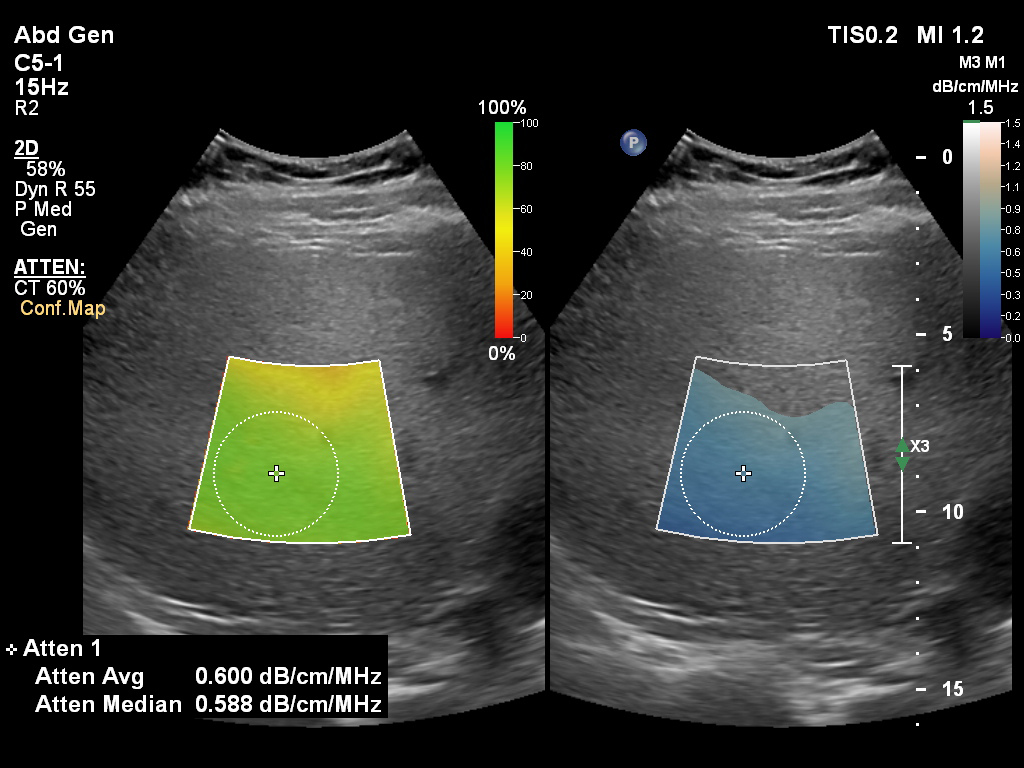

“With a quantitative way of measuring liver fat, it is a lot easier for us to let the referring physician know where the patient is quantitatively on the NAFLD spectrum,” said Richard G. Barr, MD, PhD, President, Radiology Consultant, Inc., Youngstown, Ohio, U.S.A., and Medical Director at Southwoods Imaging. “With traditional gray scale imaging, we could only tell if the liver had a high degree of fatty infiltration or if it was normal, but it was very hard to assess whether fatty liver disease was mild, moderate or severe. Attenuation imaging now gives us a numerical value that will enable us to follow the patient over time. With the combination of quantitative fat assessment and liver stiffness the probability of NASH can be assessed.”

Philips Ultrasound Systems EPIQ and Affiniti on Release 9.0 now support radiologists and hepatologists in the diagnosis and treatment from early-stage to advanced liver disease, making it easier to perform longitudinal studies to assess liver disease progression. With this latest release, the company further strengthens its liver solution and expands its full availability to the Affiniti 70 and Affiniti 50 – supported by the innovative PureWave C5-1 Curved transducer, now also available on Affiniti 50 – to enhance diagnostic confidence in abdominal, hepatology, and vascular and gynaecological ultrasound exams as well. The new Liver Fat Quantification tools complement the company’s existing ultimate solution for liver assessment with real-time shear wave imaging, contrast enhanced ultrasound (CEUS) and fusion and navigation. The Liver Fat Quantification tools, which feature ease of use plus intuitive workflow and reporting, is available on both the C5-1 and the small footprint mC7-2 MicroConvex transducer, to accommodate different body types, from smaller patients to high BMI patients [3].